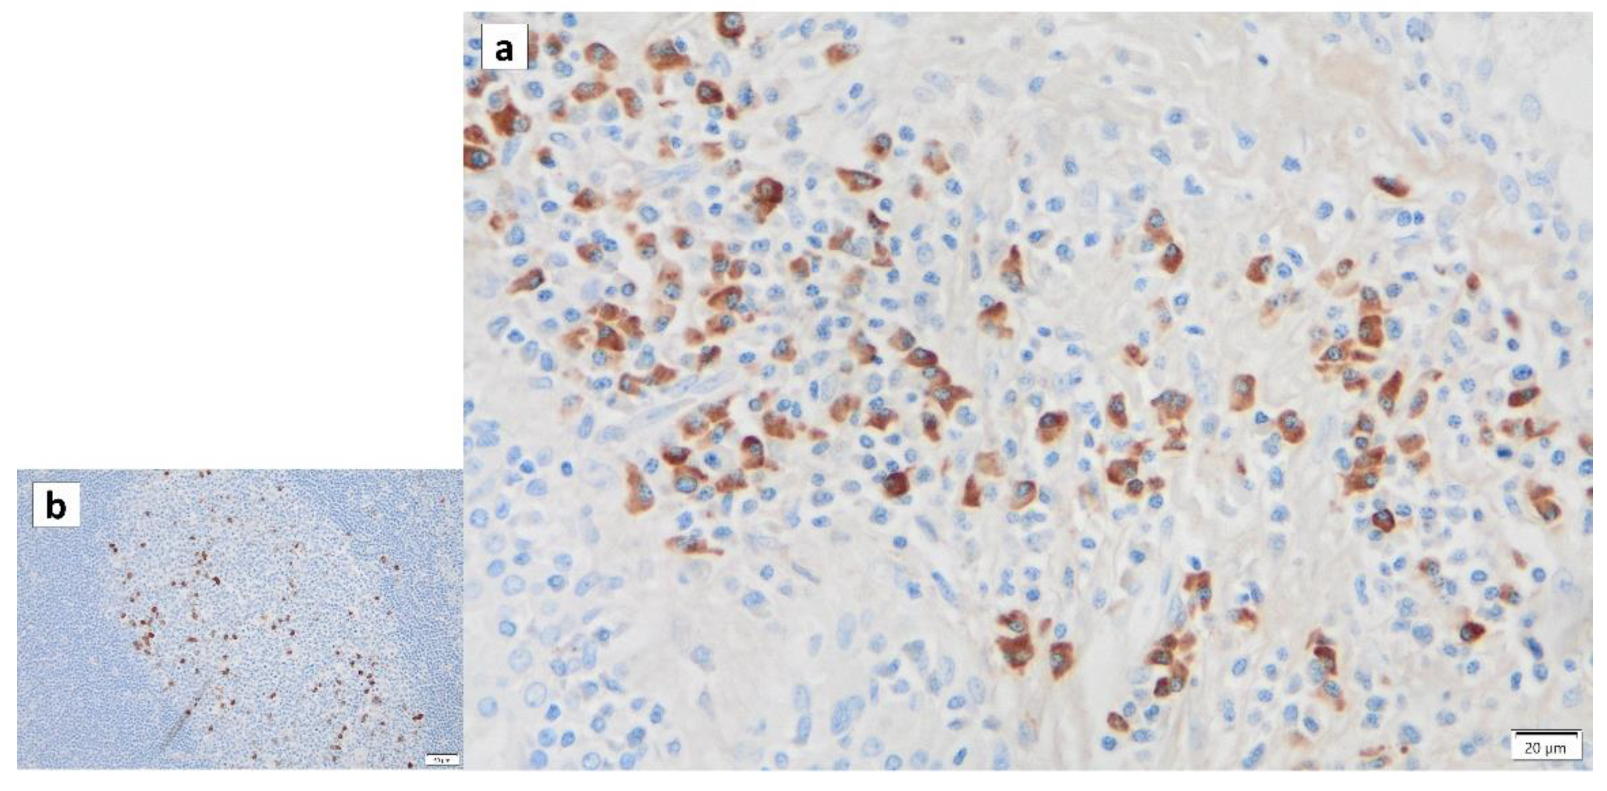

10. The Role of p16 and p53 in Warthin’s Tumor

- Mandic, R.; Agaimy, A.; Pinto-Quintero, D.; Roth, K.; Teymoortash, A.; Schwarzbach, H.; Stoehr, C.G.; Rodepeter, F.R.; Stuck, B.A.; Bette, M. Aberrant Expression of Glyceraldehyde-3-Phosphate Dehydrogenase (GAPDH) in Warthin Tumors. Cancers 2020, 12, 1112. [Google Scholar] [CrossRef]